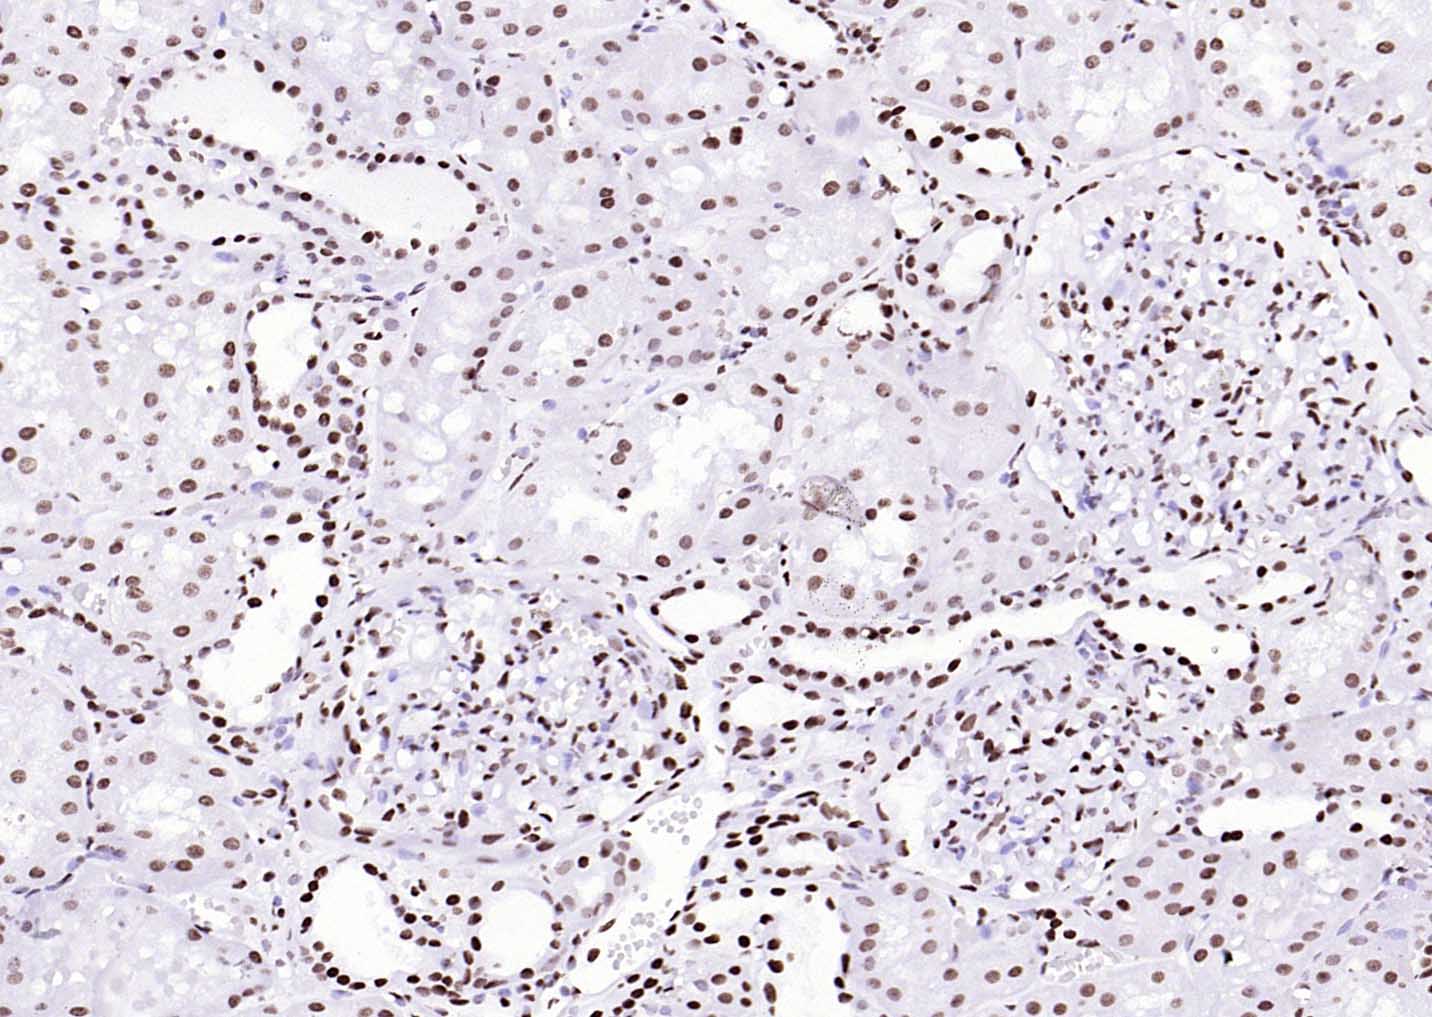

产品细节图片27

P‌‌araformaldehyde-fixed, paraffin embedded Human Colon Cancer; Antigen retrieval by boiling in sodium citrate buffer (pH6.0) for 15 min; Antibody incubation with Histone H3 Monoclonal Antibody, Unconjugated (ascites of bsm-33042M) at 1:1500 overnight at 4°C, followed by conjugation to the bs-40296G-HRP and DAB (C-0010) staining.